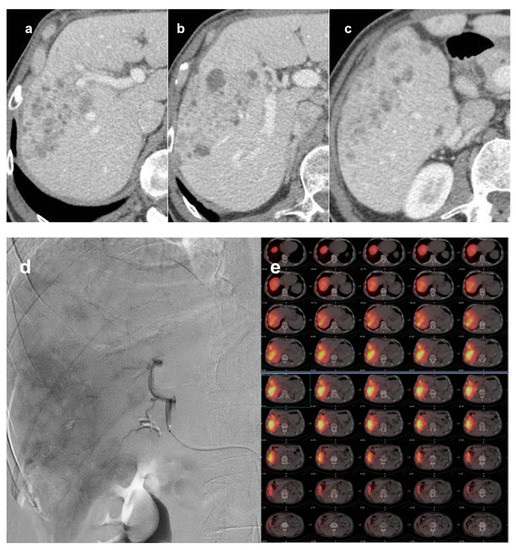

- Vasnani, R.; Ginsburg, M.; Ahmed, O.; Doshi, T.; Hart, J.; Te, H.; Van Ha, T.G. Radiofrequency and Microwave Ablation in Combination with Transarterial Chemoembolization Induce Equivalent Histopathologic Coagulation Necrosis in Hepatocellular Carcinoma Patients Bridged to Liver Transplantation. Hepatobiliary Surg. Nutr. 2016, 5, 225–233. [Google Scholar] [CrossRef] [Green Version]